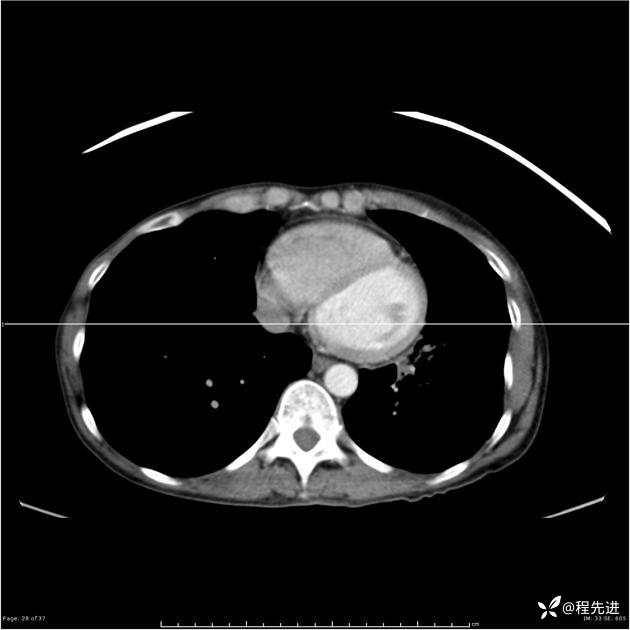

病例女,53岁,气管、左主支气管、下叶支气管内结节,乳头状瘤?期待你的精彩解读

女,53岁

乳头状瘤?